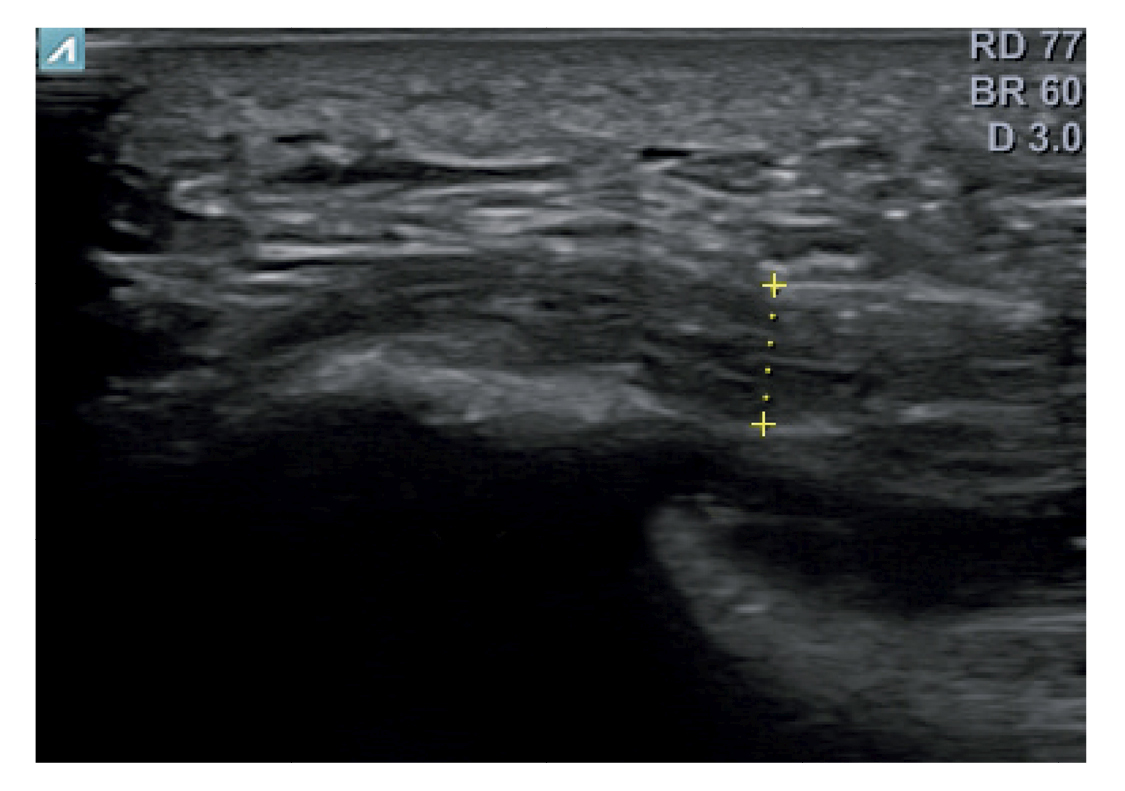

El diagnóstico se estableció en base a los síntomas y se confirmó mediante ecografía con equipo de alta resolución (Alpinion Ecube 9, ALPINION MEDICAL SYSTEMS Co., Ltd., República de Korea) con transductor lineal de 6 a 12 MHz (Figuras 2 y 3).

Figura 3. Área de medición del grosor de la fascia plantar. La línea punteada corresponde con la medición del grosor.